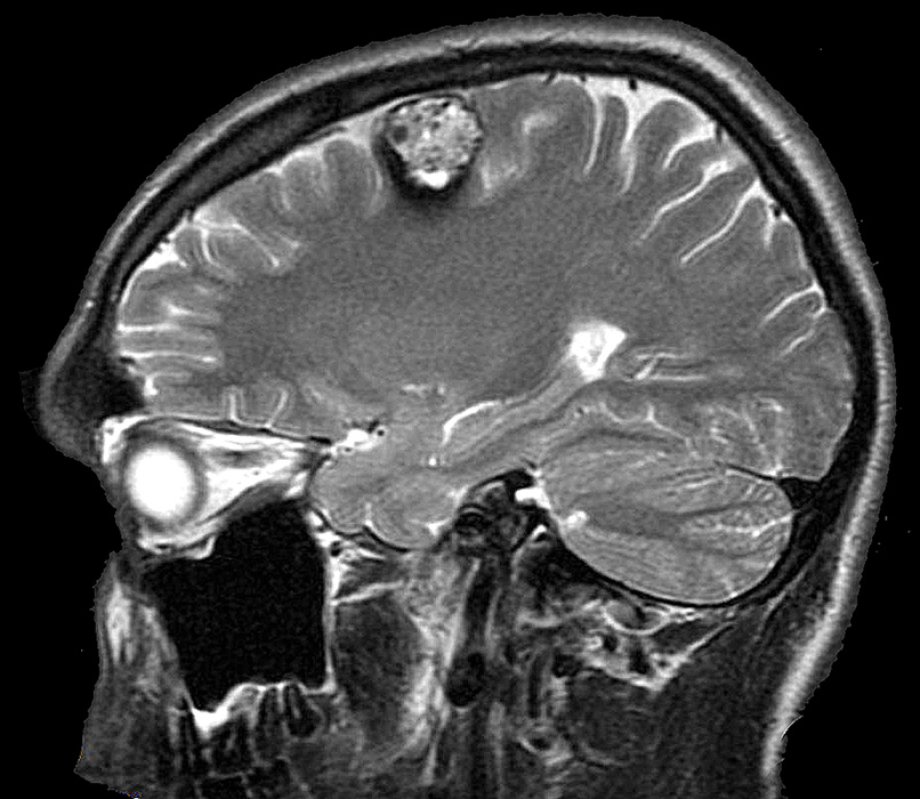

Основним методом діагностики каверноми є магнітно-резонансна томографія.

Саме МРТ дозволяє виявити утворення, оцінити його структуру, розміри та ознаки перенесених крововиливів. Для каверноми характерна специфічна картина - так званий "попкорн-ефект": утворення має неоднорідну структуру через наявність крові та продуктів її розпаду на різних стадіях, що створює мозаїчний вигляд на зображенні.